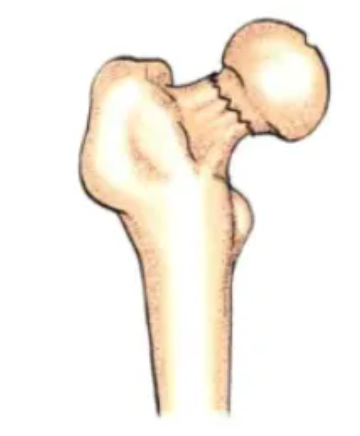

Subcapital type, transcervical type, basal type. This classification method is widely used in clinical practice because it involves the blood supply of the femoral head artery and is closely related to prognosis. The closer the fracture line is to the femoral head, the greater the likelihood of developing femoral head necrosis later.

image.pngSubcapitalTranscervicalBasal

Subcapital

The fracture line is located at the head-neck junction; this type is rare and has a high probability of complicated femoral head necrosis.

Transcervical

Also known as the intermediate neck type, where the fracture line passes through the femoral neck, this type is relatively rare.

Basal

When the fracture line is close to the intertrochanteric line, this type of fracture is an extra-capsular fracture, similar to an intertrochanteric fracture. It has good blood supply and the best prognosis.